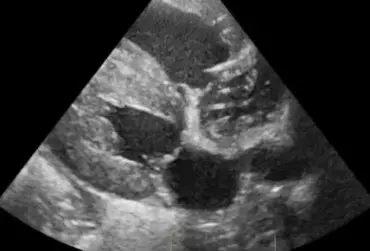

W artykule opisano przypadek dirofilariozy u psa wywołanej D. immitis. U badanego pacjenta stwierdzono patognomiczny obraz zmian w badaniu rentgenowskim i ultrasonograficznym układu sercowo-naczyniowego.